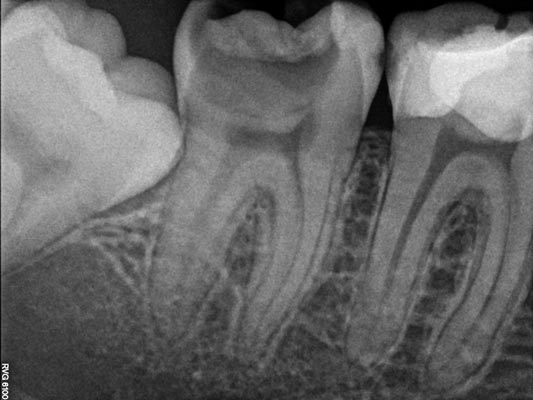

Endodoncia

Tratamiento de conductos

La endodoncia permite eliminar la pulpa dental dañada del interior del diente y de sus raíces, conservando el diente natural.

Dado que cada diente presenta una anatomía única es fundamental identificar y tratar correctamente todos los conductos radiculares para evitar infecciones y asegurar la viabilidad del diente a largo plazo.

Imágenes: Endodoncia en un molar inferior izquierdo

Reendodoncia

En los casos en los que una endodoncia previa no ha tenido el resultado esperado, es posible realizar una reendodoncia. Este procedimiento consiste en retirar el material de relleno anterior, localizar y tratar conductos que no fueron tratados inicialmente y aplicar un protocolo de desinfección riguroso antes de volver a sellar correctamente todo el sistema de conductos. La reendodoncia permite resolver infecciones persistentes y, en muchos casos, evitar la extracción, conservando el diente natural y mejorando su pronóstico a largo plazo.

Imágenes: Reendodoncia en un molar inferior derecho